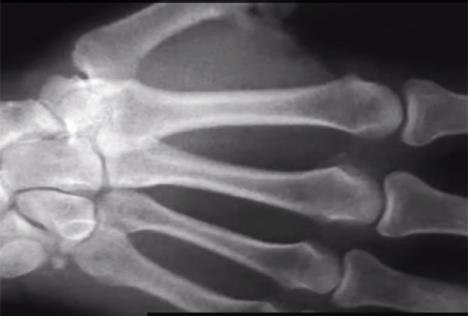

Tečnost u zglobovima zove se sniovijalna tečnost, zbog drastičnog pada pritiska kada se zglob istegne pretvara se polovično u plin. Zvuk koji čujemo ustvari su mehurići plina koji izlaze iz tečnosti.

Kako bi pobio tezu o artritisu, doktor Donald Unger 60 godina je pucao zglobovima samo na levoj ruci, a nikada na desnoj. Artritis se nije pojavio ni na jednoj, ni na drugoj. Za svoje istraživanje osvojio je Nobelovu nagradu za medicinu.